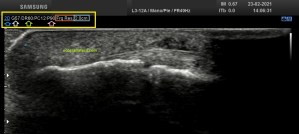

La anatomía locorregional es siempre importante, te dejo en la imagen 3 una muestra de aquella que es más importante para que intentes, en caso de que estés empezando, a reproducir dicha imagen. Ojo que la vesícula no suele estar colocada siempre tan bonita para que la veamos y hay que trabajársela, como truco, prueba a poner al paciente en decúbito lateral izquierdo.

La estructura y su patología se estudia en axial y longitudinal, se demuestra entonces los hallazgos que son confirmados por el radiólogo en su informe posterior.